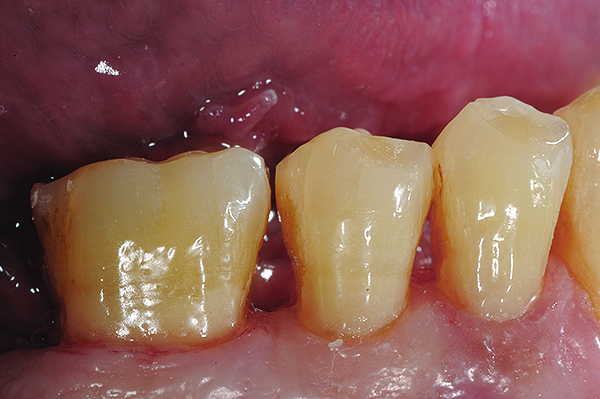

The case depicted in Figure 2 through Figure 5 was completed clinically in late 2009 and subsequently reported in a technique paper published by the author in 2010.37 The case describes the aforementioned EQUIA technique, which essentially employs a high-viscosity, posterior-grade GIC with a bulk-fill technique that is then surface-coated with a penetrating, nanofilled light-cured resin glaze. The reader is referred to the original paper for details about the case, materials, and technique. What is pertinent to this article, however, is the retention and continued durability of the restoration at approximately 42 months. Figure 2 and Figure 3 show the pretreatment view of defective Class I and Class V amalgam restorations, while Figure 4 and Figure 5 illustrate the 42-month recall of the EQUIA Fil restorations. Note that after nearly 4 years of clinical service both restorations were not only still in service but were in excellent condition and would be rated Alfa according to a modified US Public Health Service (USPHS) clinical rating criteria. There is clearly no evidence of excessive wear, staining, marginal microleakage, or recurrent decay. Though this single case is anecdotal, it supports the results found in more comprehensive clinical trials such as those referenced above.

Fig 4 and Fig 5. Occlusal (Fig 4) and buccal (Fig 5) 42-month recall views of the Class I and Class V GIC restorations placed with bulk-fill EQUIA technique.